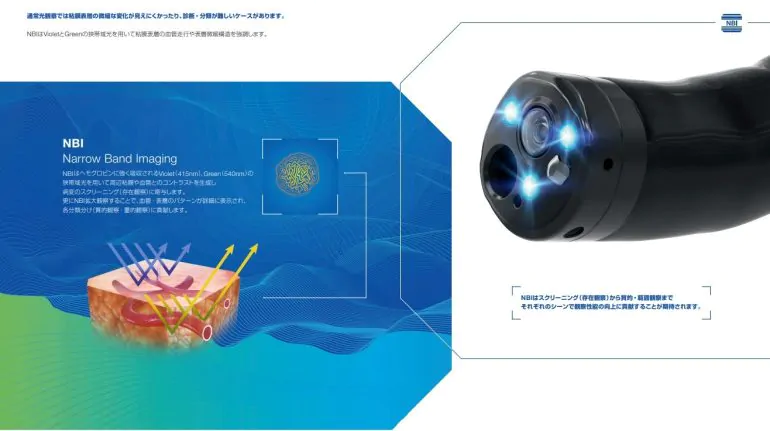

NBI(狭帯域光観察)

がんの増殖には血管からの栄養補給を必要とするため、病変の近くの粘膜には、小さな血管が集まりやすくなります。そのため、この小さな血管の集まりをいち早く発見することが、がんなどの病変の早期発見には重要です。

そのために用いられる技術が、「NBI(Narrow Band Imaging)」です。NBIは、血液中のヘモグロビンに吸収されやすい紫と緑の2つの特殊な光を照らすことで、粘膜表層の毛細血管やそのパターンなどが強調して鮮明に表示される観察技術です。これにより、通常光による観察では見えづらかったがんなどの病変の早期発見に貢献することが期待されます。

また、最適な治療判断には病変診断も重要となります。NBIは血管や粘膜の詳しい観察をサポートし、その診断にも貢献することが期待されます。